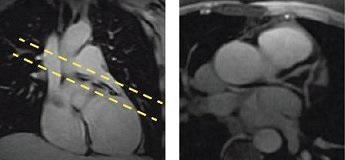

Figure 1. Sagittal localizer with axial prescription (left), axial view from sagittal localizer (right)